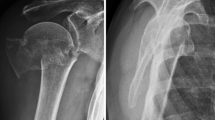

Complex proximal humerus fractures (PHF) often occur in older adults, especially in women, and are oftentimes osteoporotic in nature [1]. The main goal in treating displaced fractures or fracture dislocations is to achieve good clinical shoulder function with no pain via restoration of the proximal humeral anatomy—a goal best achieved by open reduction and internal fixation (ORIF) together with the use of locking plates [2,3,4,5,6,7,8,9]. The proximal humerus internal locking system (PHILOS) has gained wide acceptance and shown good functional outcomes (e.g., assessed using the Constant Murley Score) [10,11,12]. Nevertheless, even when using PHILOS, the reported complication rates and reoperation frequencies remain high [3, 8, 13,14,15,16]. Many of the reported complications were mechanical failures such as loss of reduction and secondary screw perforation, which are believed to be associated with poor anchorage in osteoporotic bone [17, 18]. Other risk factors include aging, low local bone mineral density (BMD), lack of anatomical reduction, poor restoration of medial cortical support, fracture severity (3- and 4-part fractures), and a varus impacted fracture [3, 4, 7,8,9, 14, 17,18,19,20].

The primary endpoint was the occurrence of mechanical failure during the first year after treatment. Mechanical failures were defined as loss of reduction (≥ 15° increase of varus malposition and a relative change of ≥ 5 mm of the greater or lesser tuberosity), humeral head impaction (≥ 5 mm difference in the outer plate edge and tangent of the humeral head), screw/plate loosening (any outward movement of screw position), and secondary screw perforation (perforation of 1 or more screws through the humeral head). The final assessment of mechanical failure for each patient was done after the last follow-up visit by two experienced independent reviewers. Radiographs were taken postoperatively and at each follow-up visit. Follow-up radiographs from each patient were compared with their postoperative radiographs to determine whether mechanical failures had occurred. Disagreement between the reviewers was resolved by consensus. The mechanical failure risk within the first year after treatment was compared between the treatment groups.